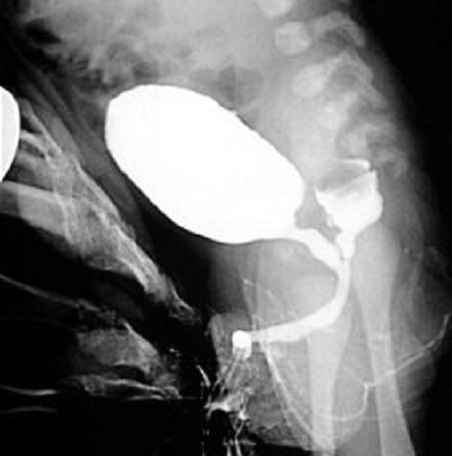

Technique radiologique

urethro-cystographie retrograde ( CPR ) : technique de

base pour verifie les fistules recto- vesicale de la vessi

Image radiologique CPR d'une

imperforation anale de type haute en association

avec fistule recto-vesicale . La fistule est situe

, a posterieure de l'urethre et inferieuse de la

prostate . |